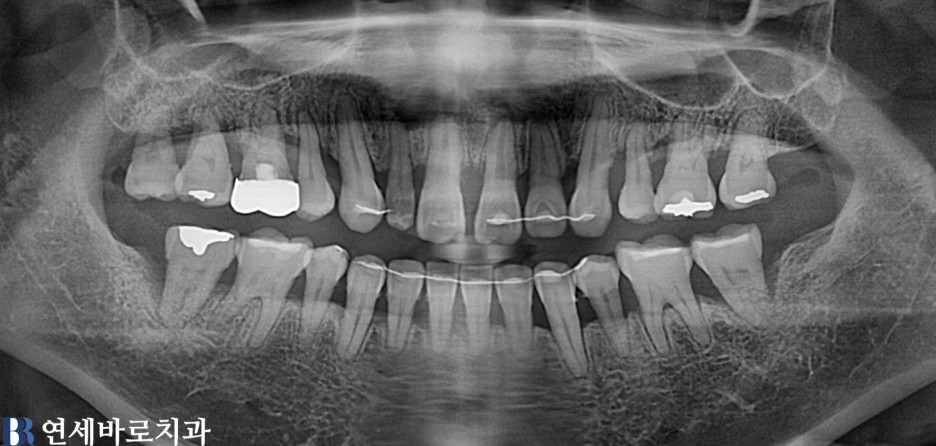

임플란트

어금니 전체 임플란트 #5